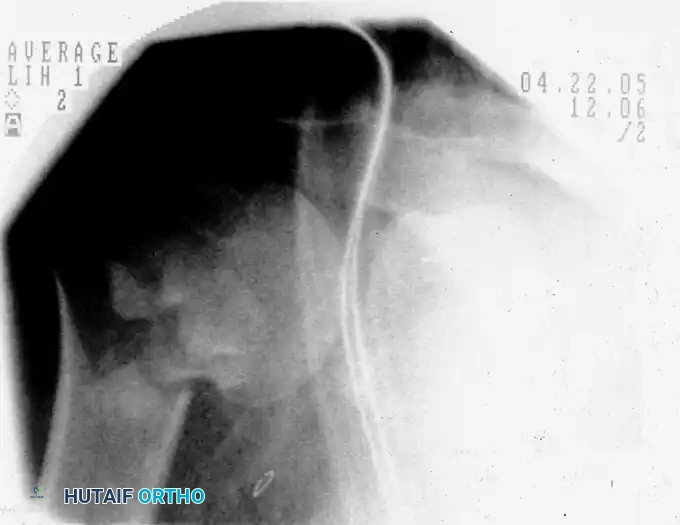

Preoperative fluoroscopic evaluation demonstrating a two-part surgical neck fracture of the proximal humerus, an ideal candidate for the anterolateral approach.

Fluoroscopic confirmation after nail insertion and the placement of multi-planar proximal locking screws.